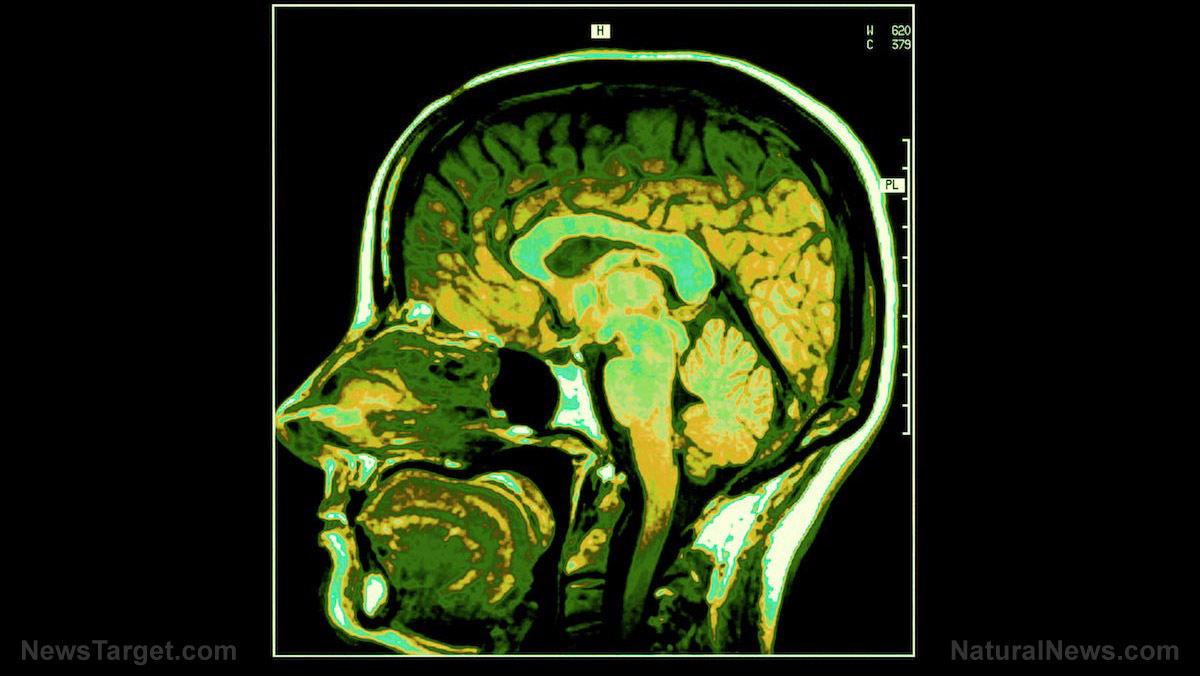

To accomplish this, researchers collected fecal samples from all the participants and measured their brain activity using a MRI scan as they viewed images that evoked an emotional response. The women were grouped according to the gut bacteria found in their feces. Thirty-three of them were recorded to have a bacterium called Bacteroides, while the remaining seven had the bacteria strain Prevotella. Surprisingly, the Bacteroids group were measured to have thicker gray matter in the frontal cortex and insula — regions of the brain that are associated with the processing of information. The Prevotella group, on the other hand, displayed more neural connections linked to emotional, attention, and sensory brain regions. Yet, this group also showed to have less active hippocampi, which is responsible for the processing of long term memory and how people respond to emotional situations. As expected, the Prevotella group reported to experience higher levels of negative feelings such as anxiety, irritability, or distress when looking at the photos.